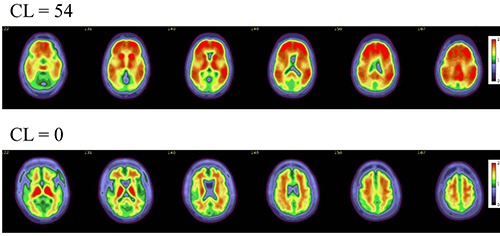

Figure 5. Axial color scales images of two brains show examples of an amyloid positive scan with a higher centiloid (CL) number and more red colors compared to a normal scan with normal background binding of the amyloid tracer signifying no amyloid plaques.